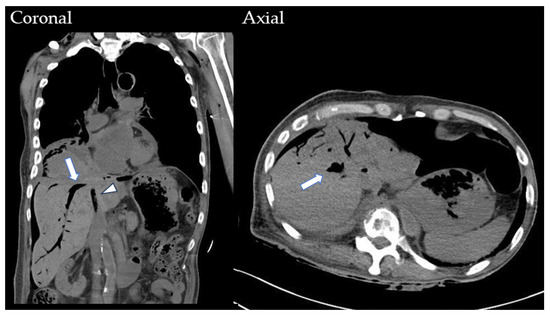

2. Case History